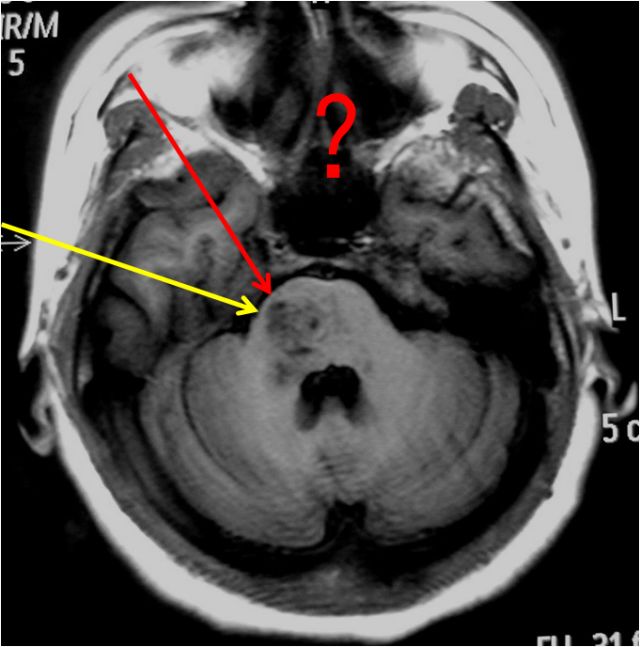

听神经瘤

手术体位个性化选择